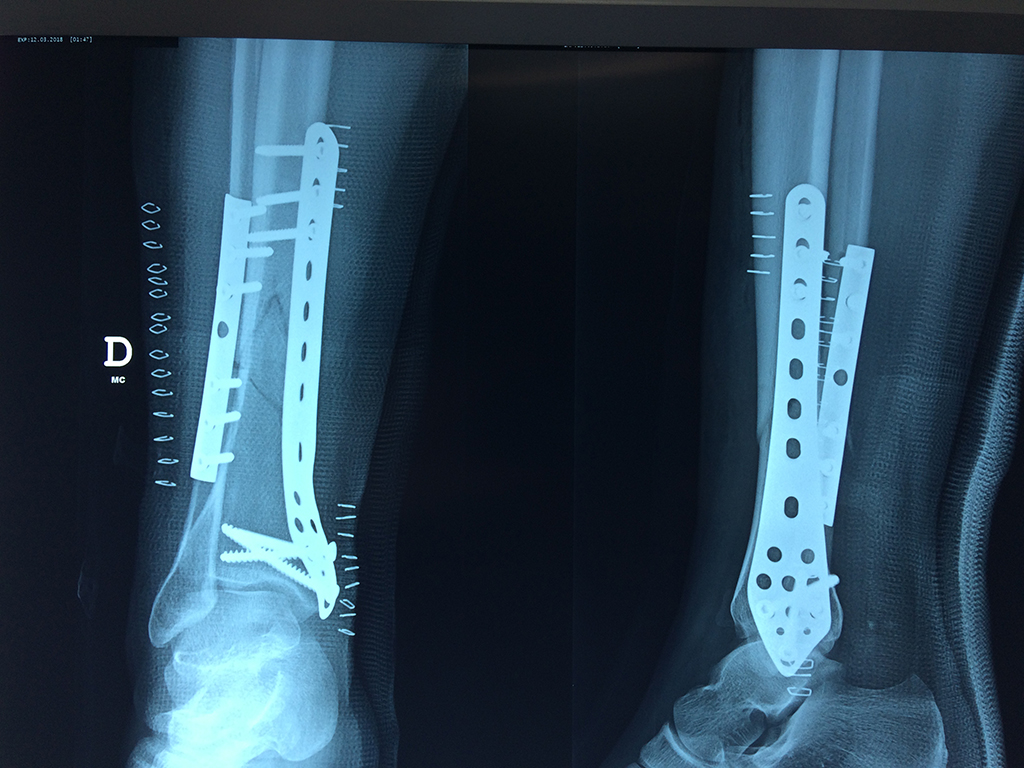

Aunque cada uno de estos huesos puede fracturarse por separado, normalmente la rotura es una lesión que se produce de forma conjunta

La mayor parte de las roturas implican a la parte proximal del hueso (parte del hueso próximo a la rodilla) o a la parte distal (parte del hueso cerca del tobillo).

Debido a la fina cobertura de piel que recubre la tibia y el peroné, las fracturas generalmente son abiertas, es decir, el hueso roto rasga la piel, atravesándola. Las fracturas de tibia y peroné generalmente se producen por un fuerte impacto o torsión.

De esta forma nos ponemos a tus órdenes, somos conocedores de estos tipos de problemas, visitarnos será un gusto el poderte ayudar. cualquier inquietud puedes escribirnos al correo Esta dirección de correo electrónico está siendo protegida contra los robots de spam. Necesita tener JavaScript habilitado para poder verlo.